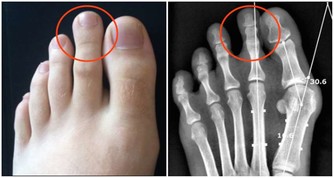

當人的年齡增大後,關節潤滑液會越來越少,潤滑度不夠,關節必定會出現磨損,這時候就會出現關節炎、骨刺、骨質疏鬆等疾病。

嚴重的甚至會導致骨關節壞死,這種屬於病理性關節響,一般伴隨著疼痛、活動受限,或者關節突然卡住。